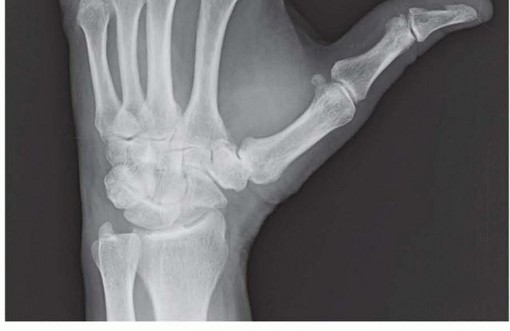

FIG 1 • Posteroanterior (PA) radiograph of wrist showing osteoarthritis of the thumb CMC joint. Stage II: joint space narrowing and osteophyte formation smaller than 2 mm Stage III: joint space narrowing with osteophytes larger than 2 mmStage IV: stage III appearance with the addition of narrowing or osteophytes in the scaphotrapezial jointThe scaphotrapezoid joint is not specifically addressed in this system and may be difficult to assess radiographically, but this joint should always be assessed at the time of surgery because it may be a source ofcontinued pain.21